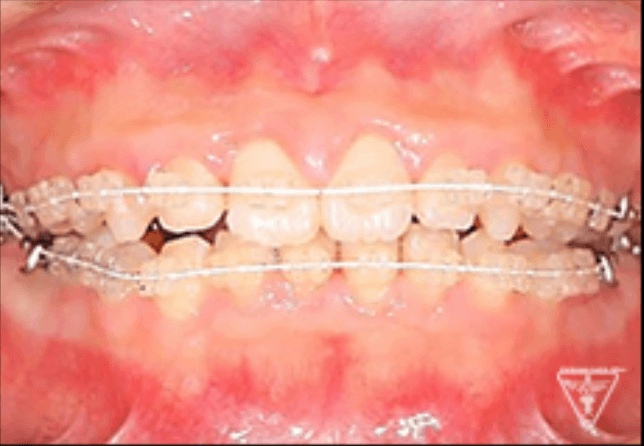

矯正器具 装着時の治療過程

初期